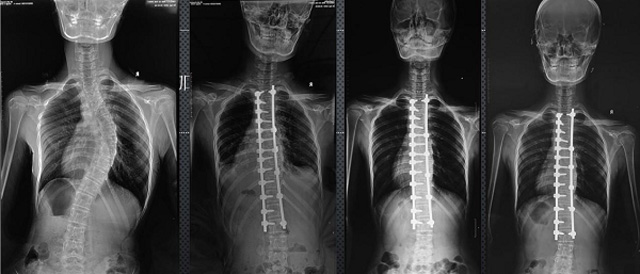

(7)全身拼接功能對有較大尺寸全脊柱拼接圖接桂成金下股分成幾次拍攝,再經(jīng)過秋件開在骨科開展的全脊柱畸形矯治工作中,雖然CT. MRI也能獲取全脊柱影像,接圖像,以便于長度、角度、力線等測量和察脊柱在重力情況下但不能進行立位檢查,無法觀全景觀察。全身拼接功能是高等級DR攝取患者立位全下的功能狀態(tài)圖像,因此采用動態(tài)醫(yī)院特別看重的動態(tài)DR功能之一。注:圖中Cobb脊柱正側(cè)位圖像是首選的檢查方法角度的大小是反映側(cè)彎嚴重程度的一個標準。